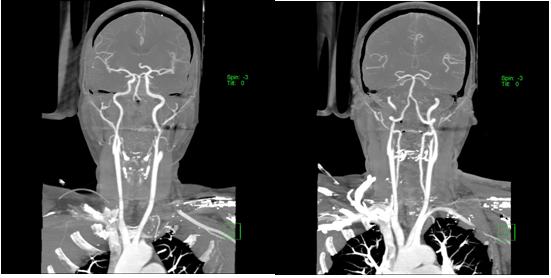

按照“先诊疗,后付费”救治原则,脑卒中救治医生全程陪护,第一时间完成头颈部CT血管成像,可以明确闭塞的基底动脉完全再通,随即收治入神经内一科重症病房,通过后续治疗,患者病情好转,生活恢复正常。

患者入院时头颈部CTA